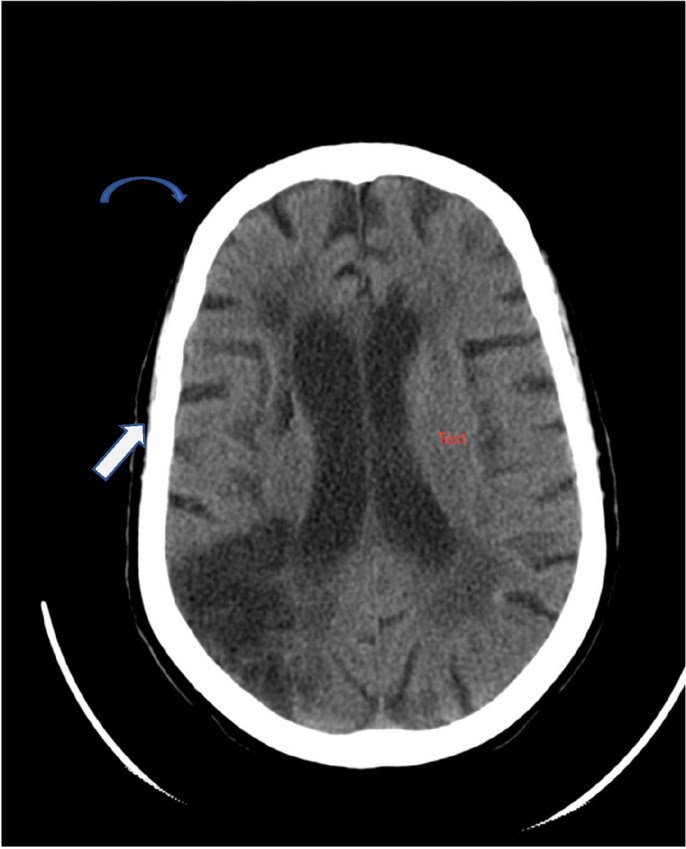

Background: Stroke remains one of the major non-communicable public health disease conditions with resultant high morbidity and mortality. Neuroimaging in the form of Computed Tomography (CT) or Magnetic Resonance Imaging (MRI) is adjudged to be the most reliable and efficient method of accurately diagnosing stroke and ruling out differentials. However, in view of cost implication and non-availability, a clinical scoring system known as the Siriraj Stroke Score (SSS) was developed to clinically differentiate stroke types, especially in resource-limited settings. This study sought to validate and determine the role of Siriraj stroke score in the clinical evaluation of patients presenting with acute stroke.

Methodology: This is a descriptive prospective study that was conducted over a one-year period. The study populations were adult patients presenting with acute stroke in a tertiary health facility in North-Western Nigeria. Clinical details with neuroimaging in the form of a CT scan were obtained. Data obtained was analyzed using Stata 15.

Results: Fifty-four percent (54%) of patients enrolled were males and ischaemic stroke is the commonest stroke subtype present in 69% of patients studied. Altered levels of consciousness, headache and vomiting are important discriminatory variables of the scoring system. The sensitivity, specificity, Positive Predictive Value (PPV), Negative Predictive Value (NPV) and accuracy of Siriraj Stroke Score for haemorrhagic stroke is 92%, 72%, 62%, 95% and 62% respectively.

Conclusion: Siriraj Stroke Score with sensitivity greater than 90% is reliable in differentiating the stroke sub-types; the patients in the 'grey zone' will however require neuroimaging.